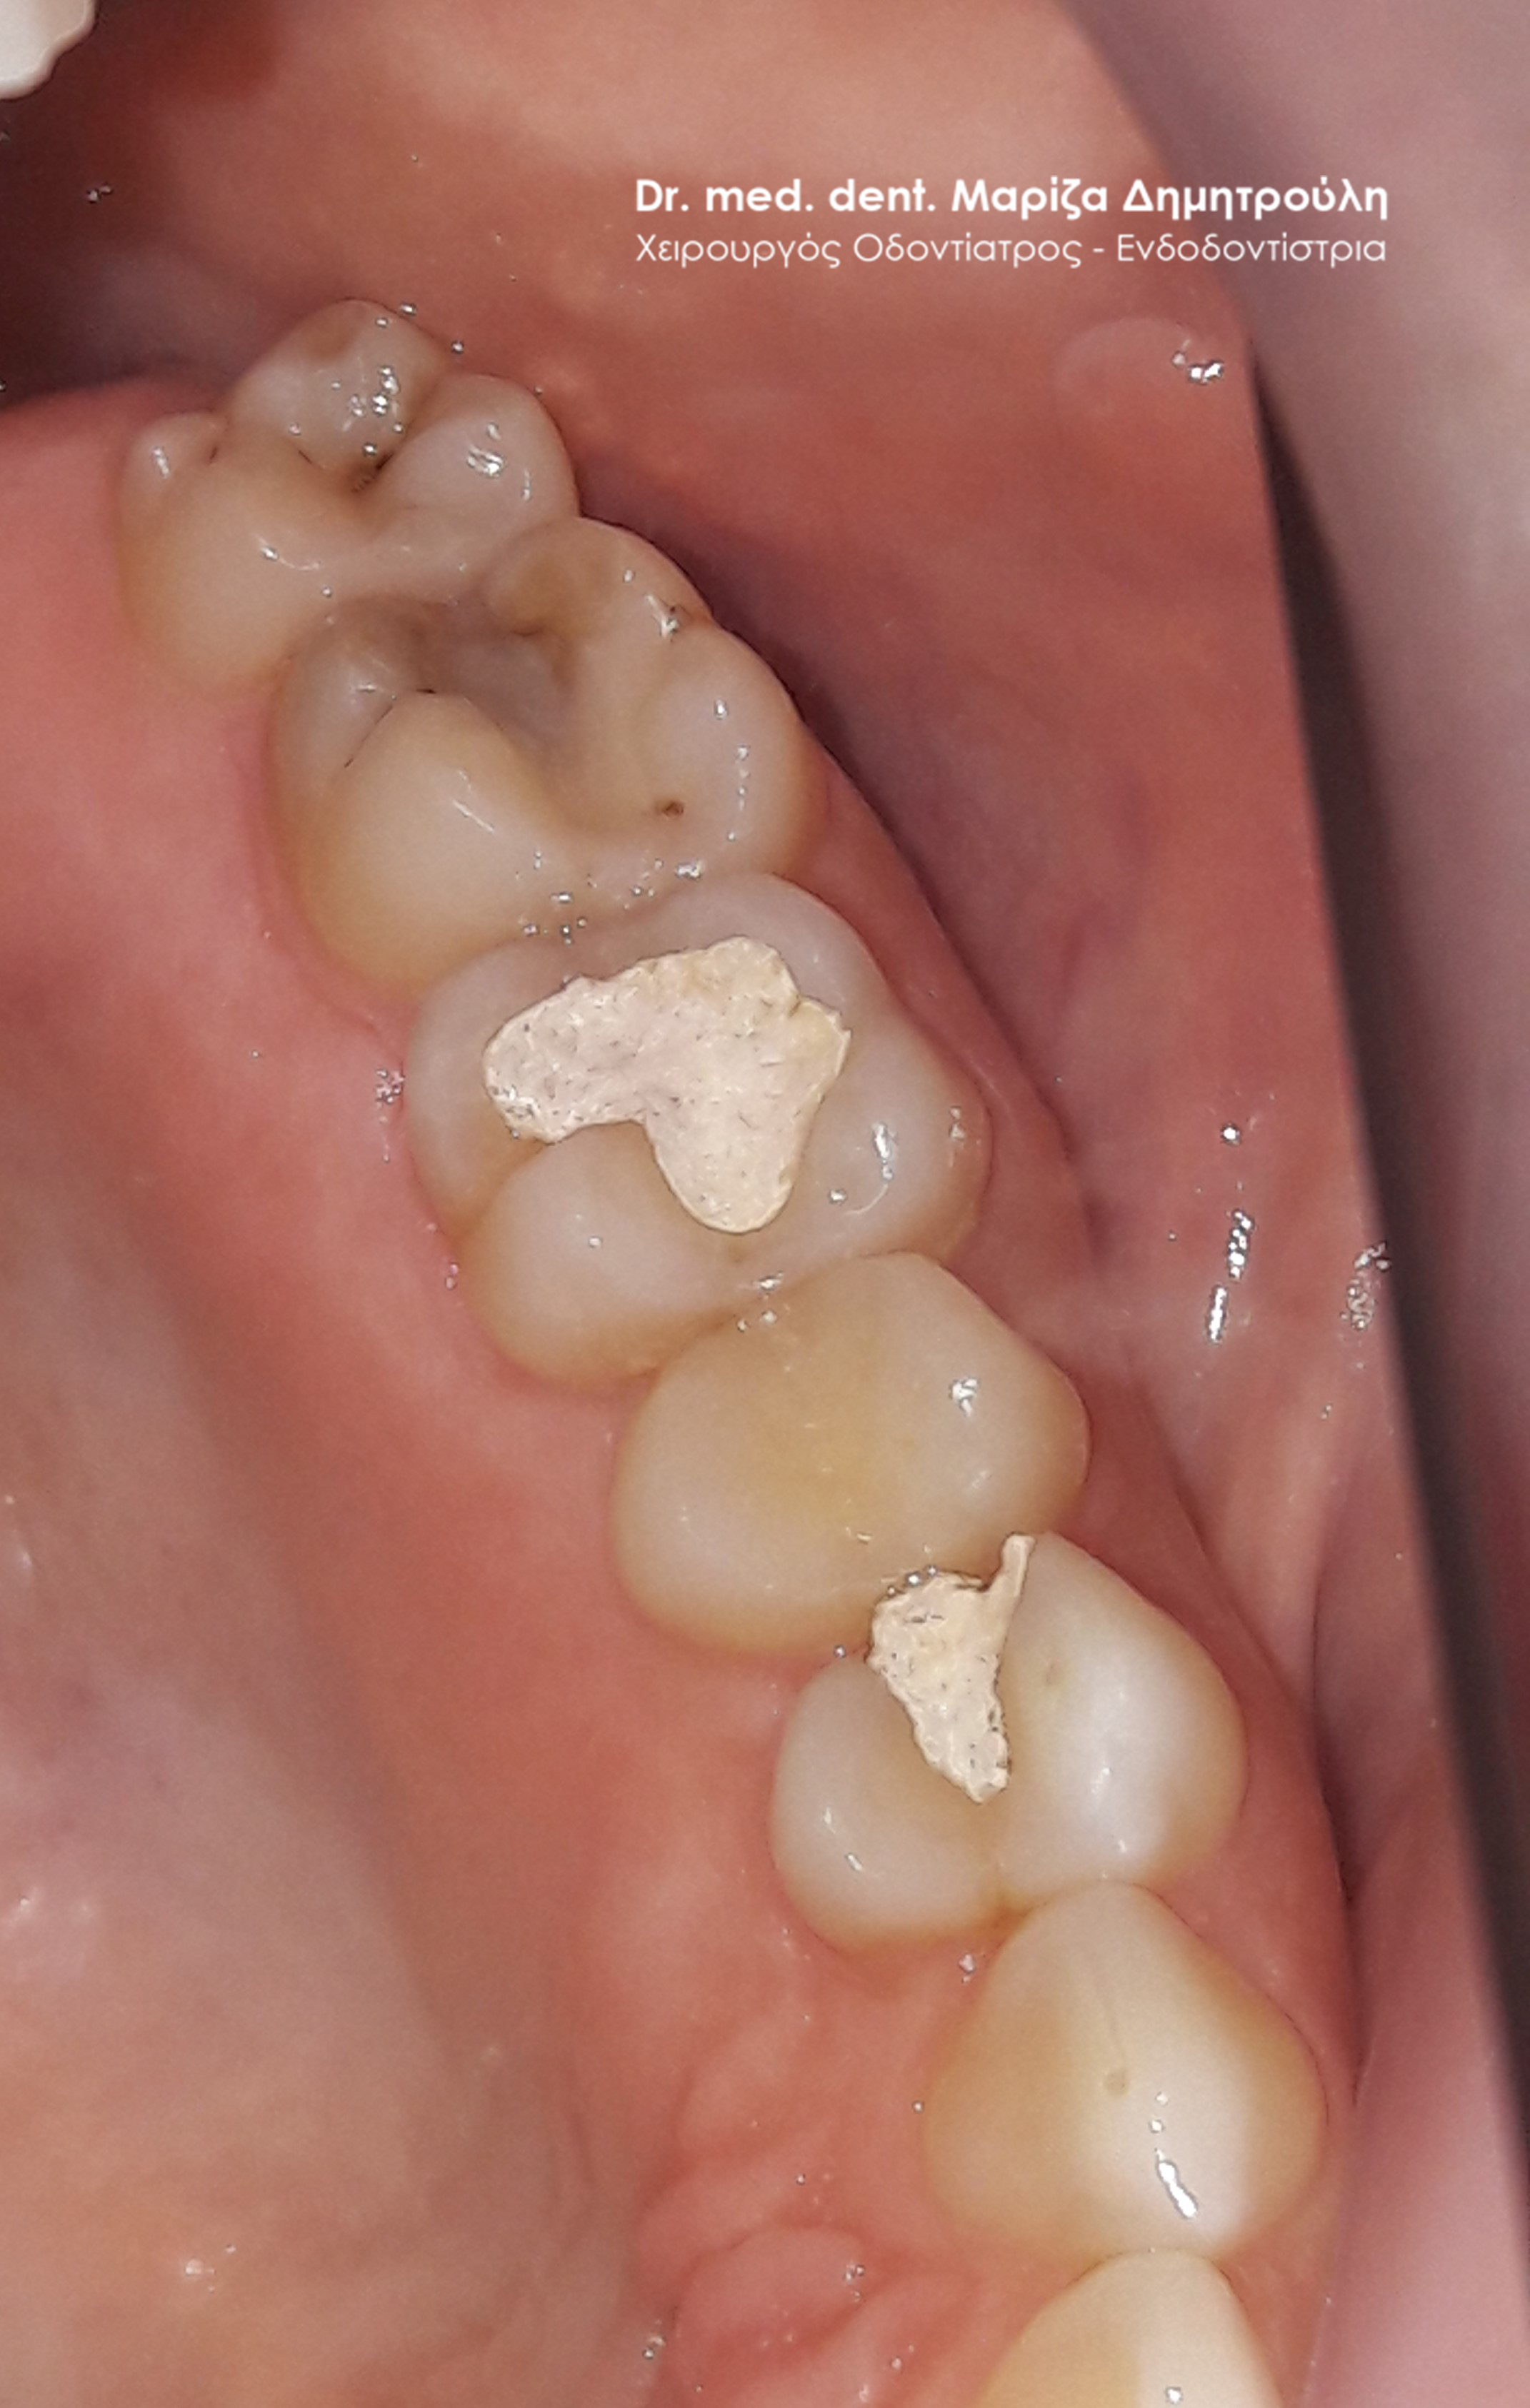

Περιστατικό – Αντικατάσταση σφραγισμάτων σε 2 δόντια

Στα πλαίσια του ετήσιου οδοντιατρικού ελέγχου διαπιστώθηκαν κάποια παλιά σφραγίσματα, τα οποία απαιτούσαν την αντικατάσταση τους εφόσον τα όρια τους ήταν ατελή και δεν είχαν ερμητική επαφή με το δόντι. Στην αρχική αριστερή φωτογραφία φαίνεται και η έντονη κίτρινη απόχρωση των παλιών σφραγισμάτων. Μετά την αφαίρεση των παλιών εμφράξεων και το καθαρισμό της τερηδόνας πραγματοποιήθηκε αποκατάσταση των δοντιών με νέα λευκά σφραγίσματα σύνθετης ρητίνης.

ΠΡΙΝ

META